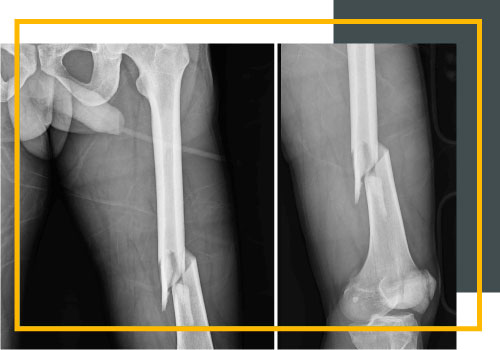

TRAUMA FRACTURAS

El Servicio de Ortopedia de Trauma está activamente comprometido con el desarrollo de técnicas quirúrgicas mínimamente invasivas para el manejo de fracturas y emplea frecuentemente las técnicas artroscópicas para las fracturas de meseta tibial. El empleo de nuevas técnicas de placas subcutáneas minimiza la cantidad de exposición quirúrgica requerida, reduciendo así el riesgo de infección y grado de sangre.

Además, el Servicio introduce permanentemente las nuevas técnicas para reducir la exposición para fracturas acetabulares que permiten el uso de incisiones más pequeñas. Con el objetivo de desarrollar un enfoque aún menos invasivo, el servicio aplica técnicas para reparar dichas fracturas en forma endoscópica.